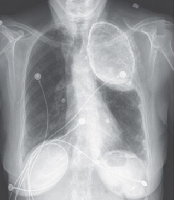

Мобильный рентгенаппарат + оцифровщик. Получение рентгеновского изображения на экране ноутбука. Вариант за 1,4 миллиона рублей под ключУРА

Мобильный рентгенаппарат с печатью рентгенограмм на рентгеновской пленке. Цена 700000 рублей.